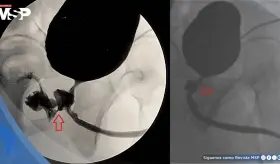

El paciente acudió dos meses después de lo programado para extracción del stent, encontrándose con una incrustación significativa y anudamiento de la punta superior en pelvis renal izquierda.

El tratamiento temporal con esponja de gelatina logró controlar la hemorragia, pero la paciente presentó recurrencia del sangrado dos semanas después; aunque se recomendó usar material embólico permanente, ella rechazó esta opción.